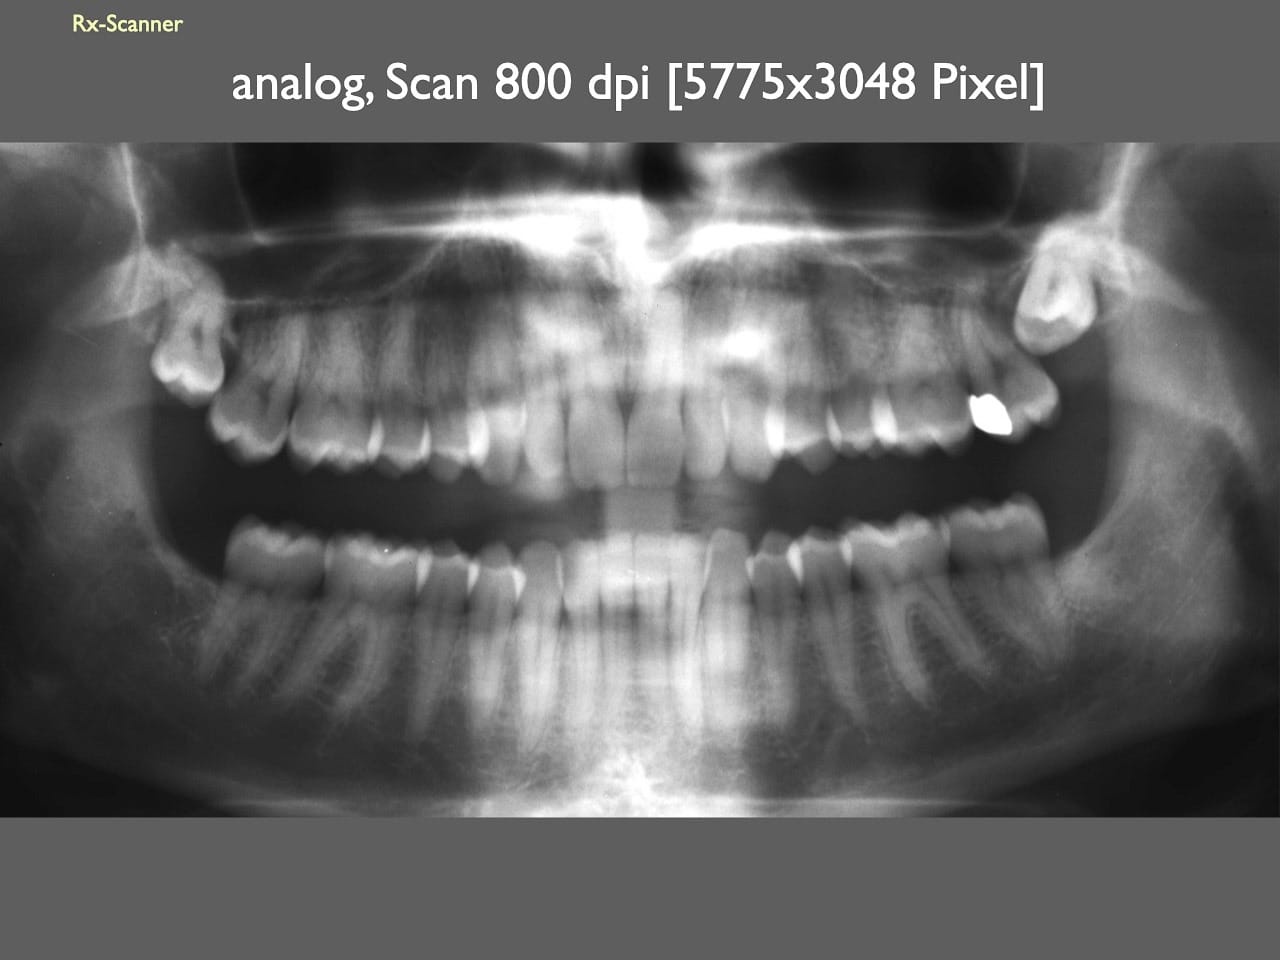

dental Scannen in der Zahnarztpraxis. Study Club vom 28.2.2010. Von peter portmann, Veröffentlicht am 28. Feb. 2010 — 3 min Lesezeit dokumentationfoto Auf dieser Seite Zahnarztpraxis-Trilogie zu Fotografie und Dokumentation Portrait Fotografie Scannen Scannen